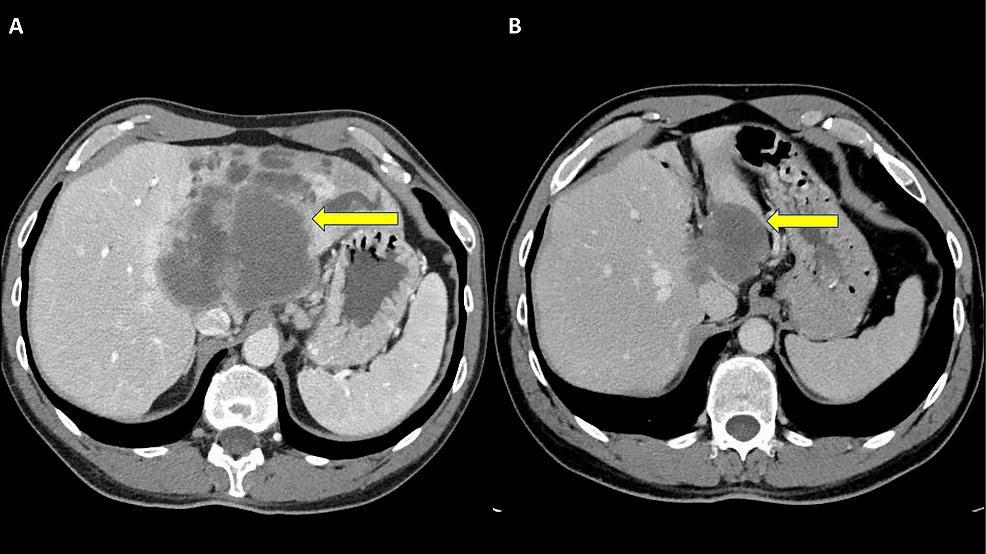

考虑到患者为TMB-H,遂停用GemCis+nab-紫杉醇化疗,开始每三周使用帕博利珠单抗200mg进行免疫治疗。后续CT扫描显示肿瘤反应,肿瘤大小在开始免疫治疗的三个月内从10*8.3cm减少到6.2*4.3cm。

在接受了5个周期的帕博利珠单抗治疗后,肿瘤在接下来的CT中显示为囊性转变,基于这种情况,肝胆外科团队重新评估患者是否可进行手术切除。标准化肝脏体积估计为57.6%,因此,患者接受了开放的扩大的左肝切除术,部分下腔静脉切除,门静脉和腹膜后淋巴结切除术,并重建右肝静脉。病理分析证实,患者对治疗有完全的反应,在标本中没有存活的肿瘤。肿瘤最大直径6.5 cm,切除的淋巴结未见癌变。患者术后未见严重不良反应,并在术后6个月继续保持良好的状态。患者计划继续使用两年的帕博利珠单抗辅助治疗。

在确诊时,肿瘤体积为10*8.3 cm,侵犯血管系统,在技术上无法切除。起初,患者接受了使用吉西他滨、顺铂和白蛋白-紫杉醇的三联姑息性化疗。在三个周期后,评估为部分反应(PR),然而,肿瘤仍然被认为是不可切除的。考虑到TMB-H状态,给予帕博利珠单抗之来哦。7个周期后,CT仍显示一个相当大的肿瘤,并伴有肝右静脉的囊性转变;然而,现在可以通过肝静脉重建手术切除。由于治疗完全缓解,病理检查无存活肿瘤,因此不提供辅助化疗。